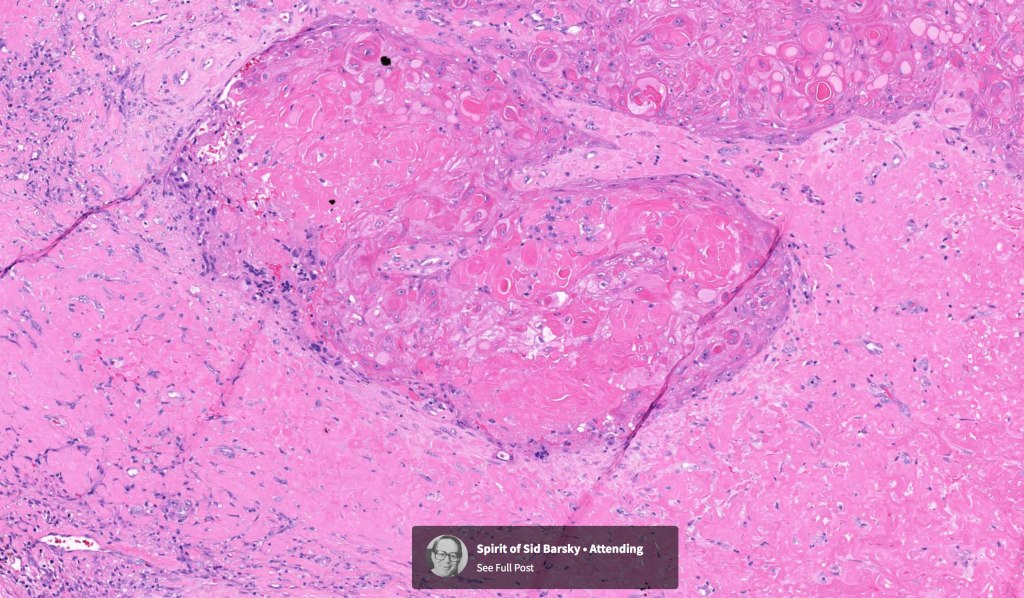

Histological features

•Infiltrating tumor arising from the wall of a pilar cyst

•Malignant change within a proliferating pilar tumor

•Stroma may be desmoplastic